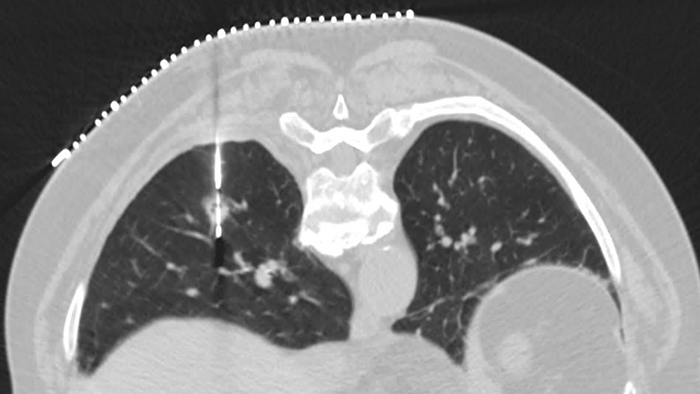

What happens when low dose and image quality work together

Experience the image quality that can be achieved with simultaneously up to 80% less dose, up to 85% less noise and up to 60% improved low-contrast detectability.3 Precise Image has a familiar image appearance that closely resembles filtered back projection (FBP). You’ll also see best-in-class low-contrast resolution.

Without Precise Image With Precise Image

Slide the bar to compare images without and with Precise Image.